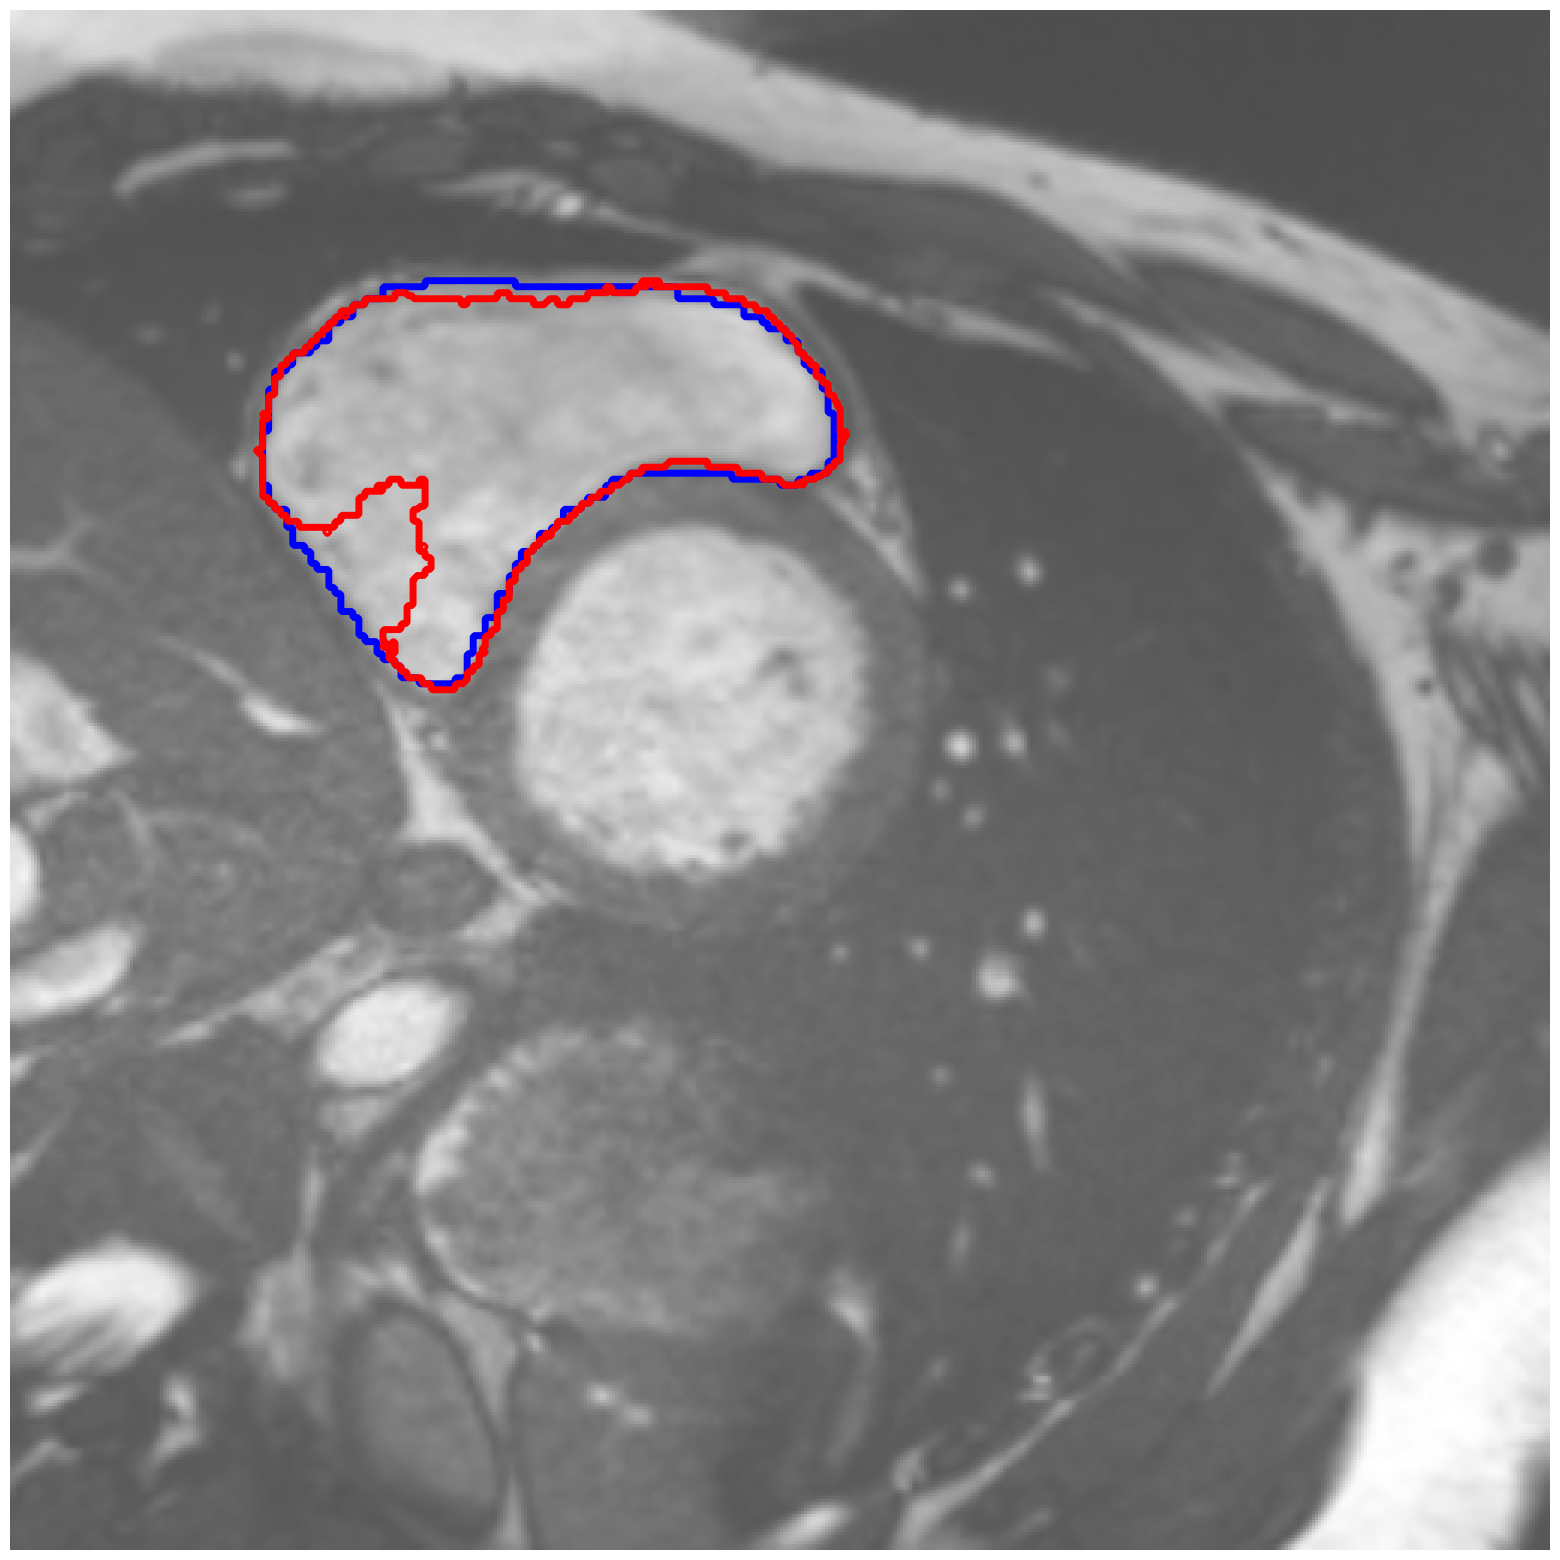

|

ACDC-RV |

![]() |

ACDC-LV |

| (a) Original pred. | b) Consema | ——— c) Standard CRC ——— | ——— d) RW-CP (Ours) ——— | |||

Visually, we observe in Fig. 1 that RW-CP is able to produce prediction sets much closer to the ground-truth than standard CRC or Consema. Our approach is even able to remove small over-segmentated areas, whereas methods such as Consema can only increase the size of the prediction set, even when the segmentation model produced false positives.

We hypothesize that the performance of RW-CP stems from its pre-processing step on probabilities, which mitigates the overconfidence commonly observed in deep learning segmentation models [16]. Their raw softmax probabilities are often skewed towards either 0 or 1 (see Fig. 1.c). This overconfidence compresses the effective range of possible values for the empirical threshold used in Conformal Risk Control, making the final prediction mask extremely sensitive to small fluctuations in . On the contrary, by first applying a diffusion process, the pixel-wise probabilities become more varied and less polarized (as shown in Fig. 1.d). This broadened distribution stabilizes the empirical during calibration, leading to a more robust and tighter prediction set, which translates to better overall segmentation metrics